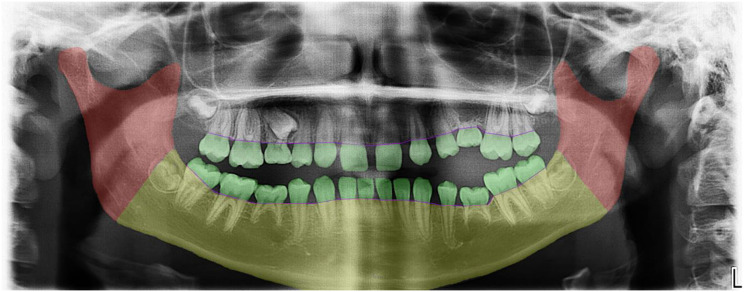

Results: Of 5645 records, 42 papers qualified for the final analysis. The evaluation of infraoccluded deciduous teeth was mainly (n = 37) performed by quantitative and semiquantitative assessment of the extent of infraposition at the occlusal level. The measurement reference differed considerably. Fewer studies have analyzed ankylosed deciduous teeth at the alveolar level by examining the contour of the alveolar ridge (n = 7) or the height of the alveolar process (n = 5). Even fewer studies (n = 4) have performed qualitative analysis at the skeletal level by evaluating the influence of the vertical skeletal growth pattern on the incidence of ankylosed deciduous teeth.

Conclusions: To carry out a comprehensive evaluation of infraoccluded deciduous teeth, an assessment of the occlusal, alveolar and potentially skeletal levels is advisable. Radiographic investigations i.e. panoramic radiographs are therefore essential as a supplement to clinical examination. There is a need for standardization and objectification of the methods for the classification of infraoccluded deciduous teeth to give a general recommendation of clinical performance.